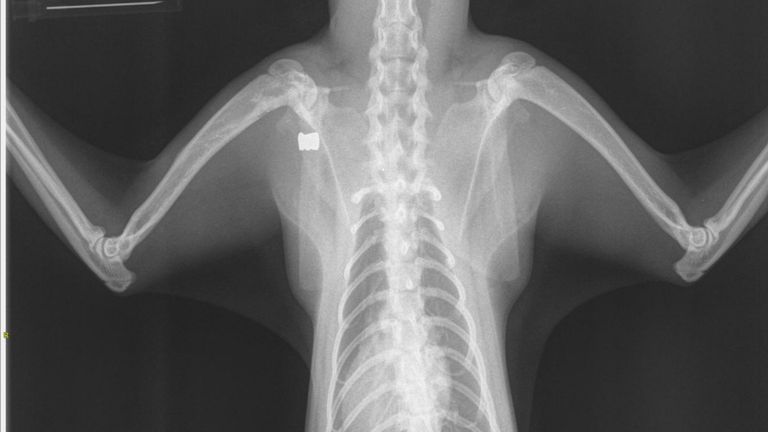

De zwart met witte kat is daarom gevangen en naar de dierenarts gebracht. Dierenarts Stijn Peters bevestigt dat het dier een kogeltje in zijn lijf bleek te hebben. De kogel werd maandag gevonden op röntgenfoto’s.

“Het gaat om een kleine luchtbukskogel boven zijn borst. De kogel zit op een plek waar je moeilijk bij komt, er zitten belangrijke spieren in de weg. Dan is het beter om de kogel te laten zitten”, legt de dierenarts uit. Volgens de arts is de kat ongeveer een jaar oud. De kat maakt het inmiddels beter, maar zal altijd mank blijven lopen.